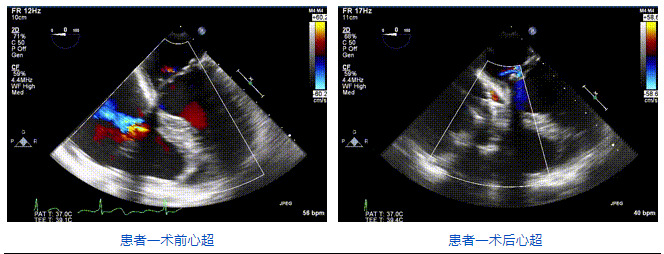

2021年12月24日,復(fù)旦大學(xué)附屬中山醫(yī)院葛均波院士團隊成功應(yīng)用LuX-Valve Plus為一例極重度三尖瓣反流(TR)合并房顫、房缺的患者完成了經(jīng)血管三尖瓣置換術(shù),這是在前基礎(chǔ)上,本周完成的第三例經(jīng)血管三尖瓣置換手術(shù),葛均波院士、周達新教授等與心外科魏來教授、賴顥教授,心超室的潘翠珍教授、李偉教授及麻醉科的郭克芳教授共同完成了本周手術(shù),均獲得圓滿成功!患者術(shù)后超聲顯示無TR,臨床癥狀明顯改善。本周手術(shù)的成功也為LuX-Valve Plus救治性臨床研究添上了濃墨重彩的一筆。

本周三例接受LuX-Valve Plus經(jīng)血管三尖瓣置換術(shù)的患者中,第一例患者為冠狀動脈旁路移植術(shù)+Bentall+二尖瓣成形術(shù)后;第二例患者為永久起搏器植入術(shù)后,存在跨三尖瓣導(dǎo)線;第三例患者合并房顫、房缺及左心耳封堵術(shù)后。

三例患者入院后,葛均波院士團隊周達新教授、潘文志教授、張源博士、陳莎莎博士及心超室的潘翠珍教授、李偉教授對患者的情況進行詳細評估和討論,最終決定為三例患者選擇LuX-Valve Plus40mm、50mm和50mm型號的瓣膜進行手術(shù)治療。手術(shù)后即刻拔除氣管插管,術(shù)后患者三尖瓣反流癥狀得到顯著改善,復(fù)查心超結(jié)果顯示人工三尖瓣瓣膜支架固定穩(wěn)定,瓣葉關(guān)閉形態(tài)未見異常,未見明顯反流。